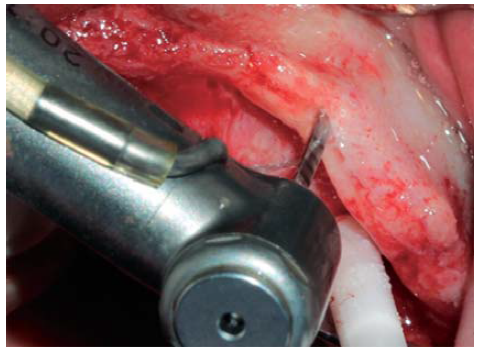

Se realizó una incisión supracrestal a espesor total, elevación del colgajo mucoperióstico exponiendo la tabla ósea hasta 4 mm de la cima de la cresta hacia vestibular y desde ese punto se dividió el colgajo a espesor parcial (Figura 3). Luego se marcaron los puntos de impacto en los sitios designados según la guía quirúrgica para la colocación de los implantes y se iniciaron las perforaciones con una fresa de 1.6 mm de diámetro para determinar el eje y profundidad deseada para los implantes. Luego se procedió a crear un surco a nivel crestal con un disco de diamante rompiendo el hueso cortical para crear el acceso a los escoplos al hueso esponjoso y con éstos se procede a separar las tablas óseas hasta llegar a una profundidad de 5 mm (Figuras 4 y 5). Seguidamente, se continuaron las perforaciones con una fresa de 2.0 mm de diámetro (Figura 6) y se realizó la expansión de la tabla vestibular creando una fractura en tallo verde con los expansores hasta alcanzar el diámetro del lecho óseo suficiente para poder utilizar la última fresa de 3.2 mm de diámetro (Figuras 7 y 8). Posteriormente, se colocaron los implantes a una velocidad de 25 rpm y a un torque de 35 Ncm (Figuras 9 y 10). Seguido de esto, se colocó un injerto óseo bovino particulado (Bonefill® Bionnovation Biomedical, Sao Paulo-Brazil), con la finalidad de preservar la integridad de las tablas óseas vestibulares (Figura 11). Todos estos procedimientos, se realizaron de la misma manera para la colocación de los seis implantes. Finalmente, se suturó con nylon monofilamento 5/0.

Figura 4 Disco de diamante de 0.5 mm de grosor utilizado para crear el surco crestal atravesando el hueso cortical permitiendo el acceso para el cincel óseo.

Figura 7 Ensanchamiento óseo utilizando expansores, creando un acceso adecuado para una fresa de mayor diámetro.

Figura 8 Expansor óseo ubicado distalmente en relación con la preparación previniendo una fractura de la tabla vestibular.